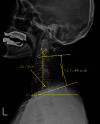

Purpose: To determine the effect of age on sagittal cervical alignment after cervical laminoplasty procedure so as to identify the group with the greatest degree of variation. Study Setting. Single-center retrospective chart review in a tertiary referral hospital. Outcome Measures. The sagittal vertical axis (SVA) (C2-7), T1 slope, and cervical lordosis.

Methods: We included patients who underwent cervical laminoplasty between 2014 and 2018 and divided 60 consecutive patients into two groups using the cut-off age of 65 years. The Paired t-test and Mann-Whitney U test were used to compare changes between preoperative radiographic cervical sagittal parameters and those 1 year after surgery.

Results: Mean patient ages in the older and younger groups were 71 years and 52 years, respectively. The difference of C2-7 SVA was greater in the older group.